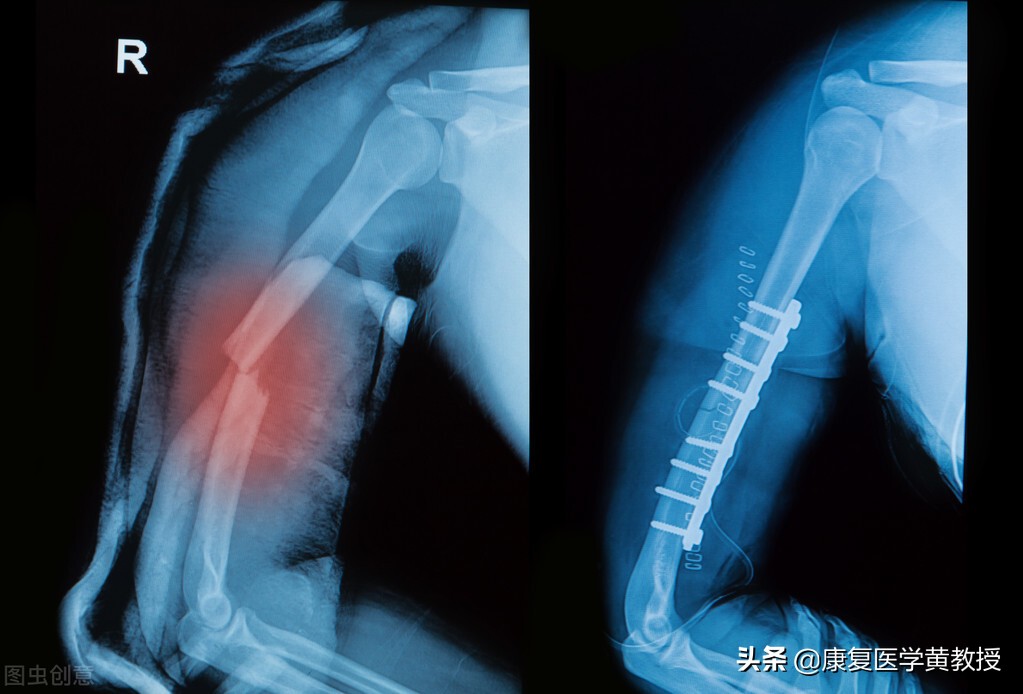

骨头是支撑身体的支架,而肌肉附着在骨头上是用来产生动作的,上肢大部分的肌肉与日常生活表现相关,而下肢与人类行走移动相关,肌肉是由神经系统支配,最终动作的执行由大脑皮质神经加以统合整理输出,为了与大自然环境和谐相处,人类是透过感觉输入-大脑整合-动作输出这样複杂的运作,才得以生存下来.骨折之后由于骨头发生位移,错位,血管破坏,甚至软组织损伤,发生血肿与循环不良,大部分骨科医生都会採取复位及制动处置(打石膏或钢板植入),需要休息的时间根据部位不同,大月是1-6个月不等.

骨折的部位通过复位固定之后,需要的是休养,因为此时骨头透过时间,会发生自癒现象,包含产生骨痂,骨质增生,血管开始发生修复,通常这个时候不宜动发生骨折位置是比较能保证骨质癒合的,可以定期接受复查,以确保骨质增生的效率,或可提早防范癒合不良的风险.

除非是大范围的粉碎性骨折,或者是多关节的连续性骨折,如果只是单一部位骨折,骨科与康復科专家都建议早期康復训练的介入,由于肌肉丧失能力发生萎缩的速度极快,通常我们康復科所採取的都是,在骨折部位的远端关节去进行维持性的功能肌力训练,而骨折部位可以进行不发生关节移动的等长收缩训练,只有早期介入,并且坚持不懈的执行,才有可能减缓肌肉萎缩的现象,只是临床上发现,患者的医从性不高,总认为自己受伤了静养,甚至受伤筋動骨100天传统观念的影响,于是当骨头癒合之后,所有的肌肉都发生萎缩,大大的增加了未来康復训练的时程.